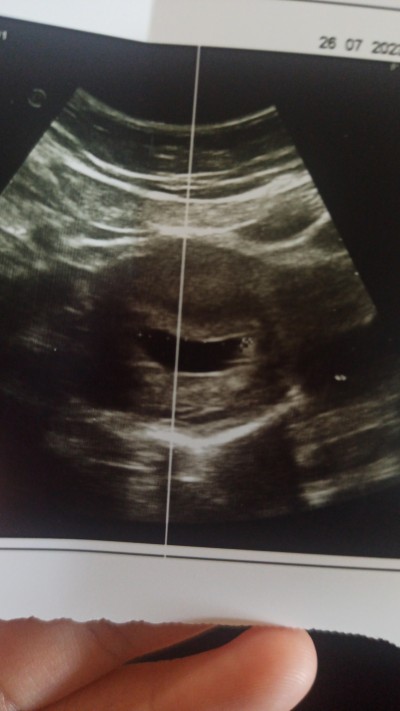

Gebeliğin 6. Haftasındayım kese 27mm ölcüldü ama bebek yok boş gebelik midir aranızda böyle bir durum yaşayan varmı ?

Gebelik haftası 7

Bebek 7. Hatta 8. Hafta bazisiznin 9. Hafta gozukur.

Çok küçük bir nokta var gibi 1 hafta sonra tekrar bakılacak dedi